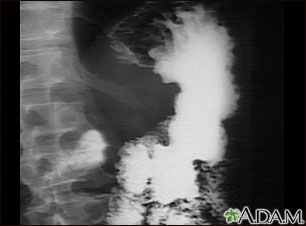

Rayos X de un cáncer de estómago

Esta es una serie GI superior en un paciente con cáncer de estómago (carcinoma gástrico).